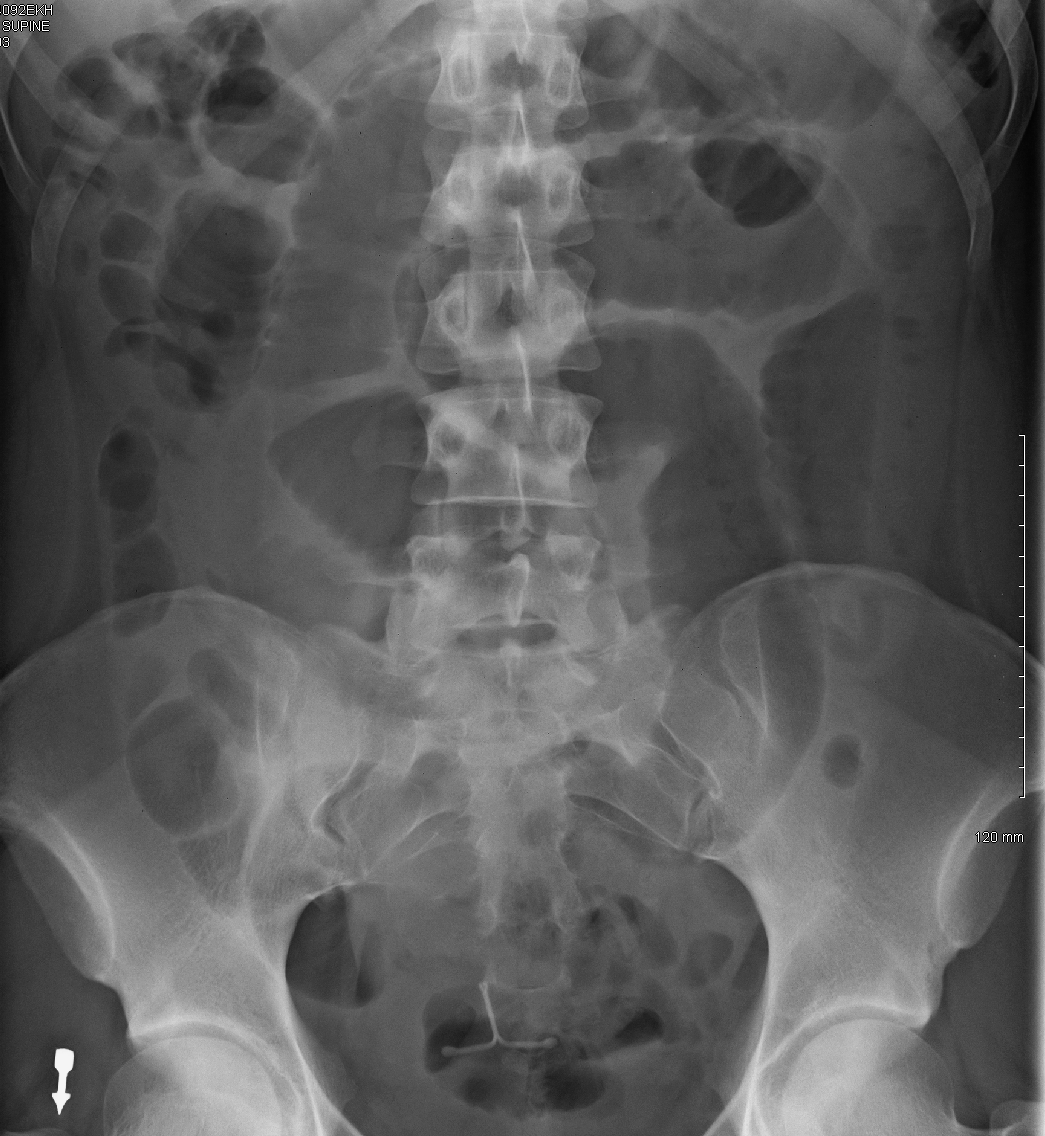

Abdomen X Ray Anatomy Labeled . Radiographic anatomy of the chest and abdomen: This article lists a series of labeled imaging anatomy cases by body region. This view is useful in assessing abdominal pathologies, including bowel obstructions, calcifications and neoplastic changes. Learn about the soft tissue structures that can. It is also used as a scout/baseline. 27 public playlists include this case. Citation, doi, disclosures and article data. The standard abdominal radiograph (axr) taken is a supine projection:

Radiographic Anatomy Abdomen AP Supine SBS Imagenologia, Radiología Abdomen X Ray Anatomy Labeled Radiographic anatomy of the chest and abdomen: The standard abdominal radiograph (axr) taken is a supine projection: 27 public playlists include this case. It is also used as a scout/baseline. This article lists a series of labeled imaging anatomy cases by body region. Learn about the soft tissue structures that can. Citation, doi, disclosures and article data. This view is. Abdomen X Ray Anatomy Labeled.

Labeled Abdominal XRay Anatomy KUB Anatomy Radiology GrepMed Abdomen X Ray Anatomy Labeled Learn about the soft tissue structures that can. 27 public playlists include this case. The standard abdominal radiograph (axr) taken is a supine projection: It is also used as a scout/baseline. This article lists a series of labeled imaging anatomy cases by body region. Citation, doi, disclosures and article data. Radiographic anatomy of the chest and abdomen: This view is. Abdomen X Ray Anatomy Labeled.

Supine Abdomen X Ray Anatomy Abdomen X Ray Anatomy Labeled This article lists a series of labeled imaging anatomy cases by body region. It is also used as a scout/baseline. 27 public playlists include this case. Citation, doi, disclosures and article data. This view is useful in assessing abdominal pathologies, including bowel obstructions, calcifications and neoplastic changes. Radiographic anatomy of the chest and abdomen: Learn about the soft tissue structures. Abdomen X Ray Anatomy Labeled.